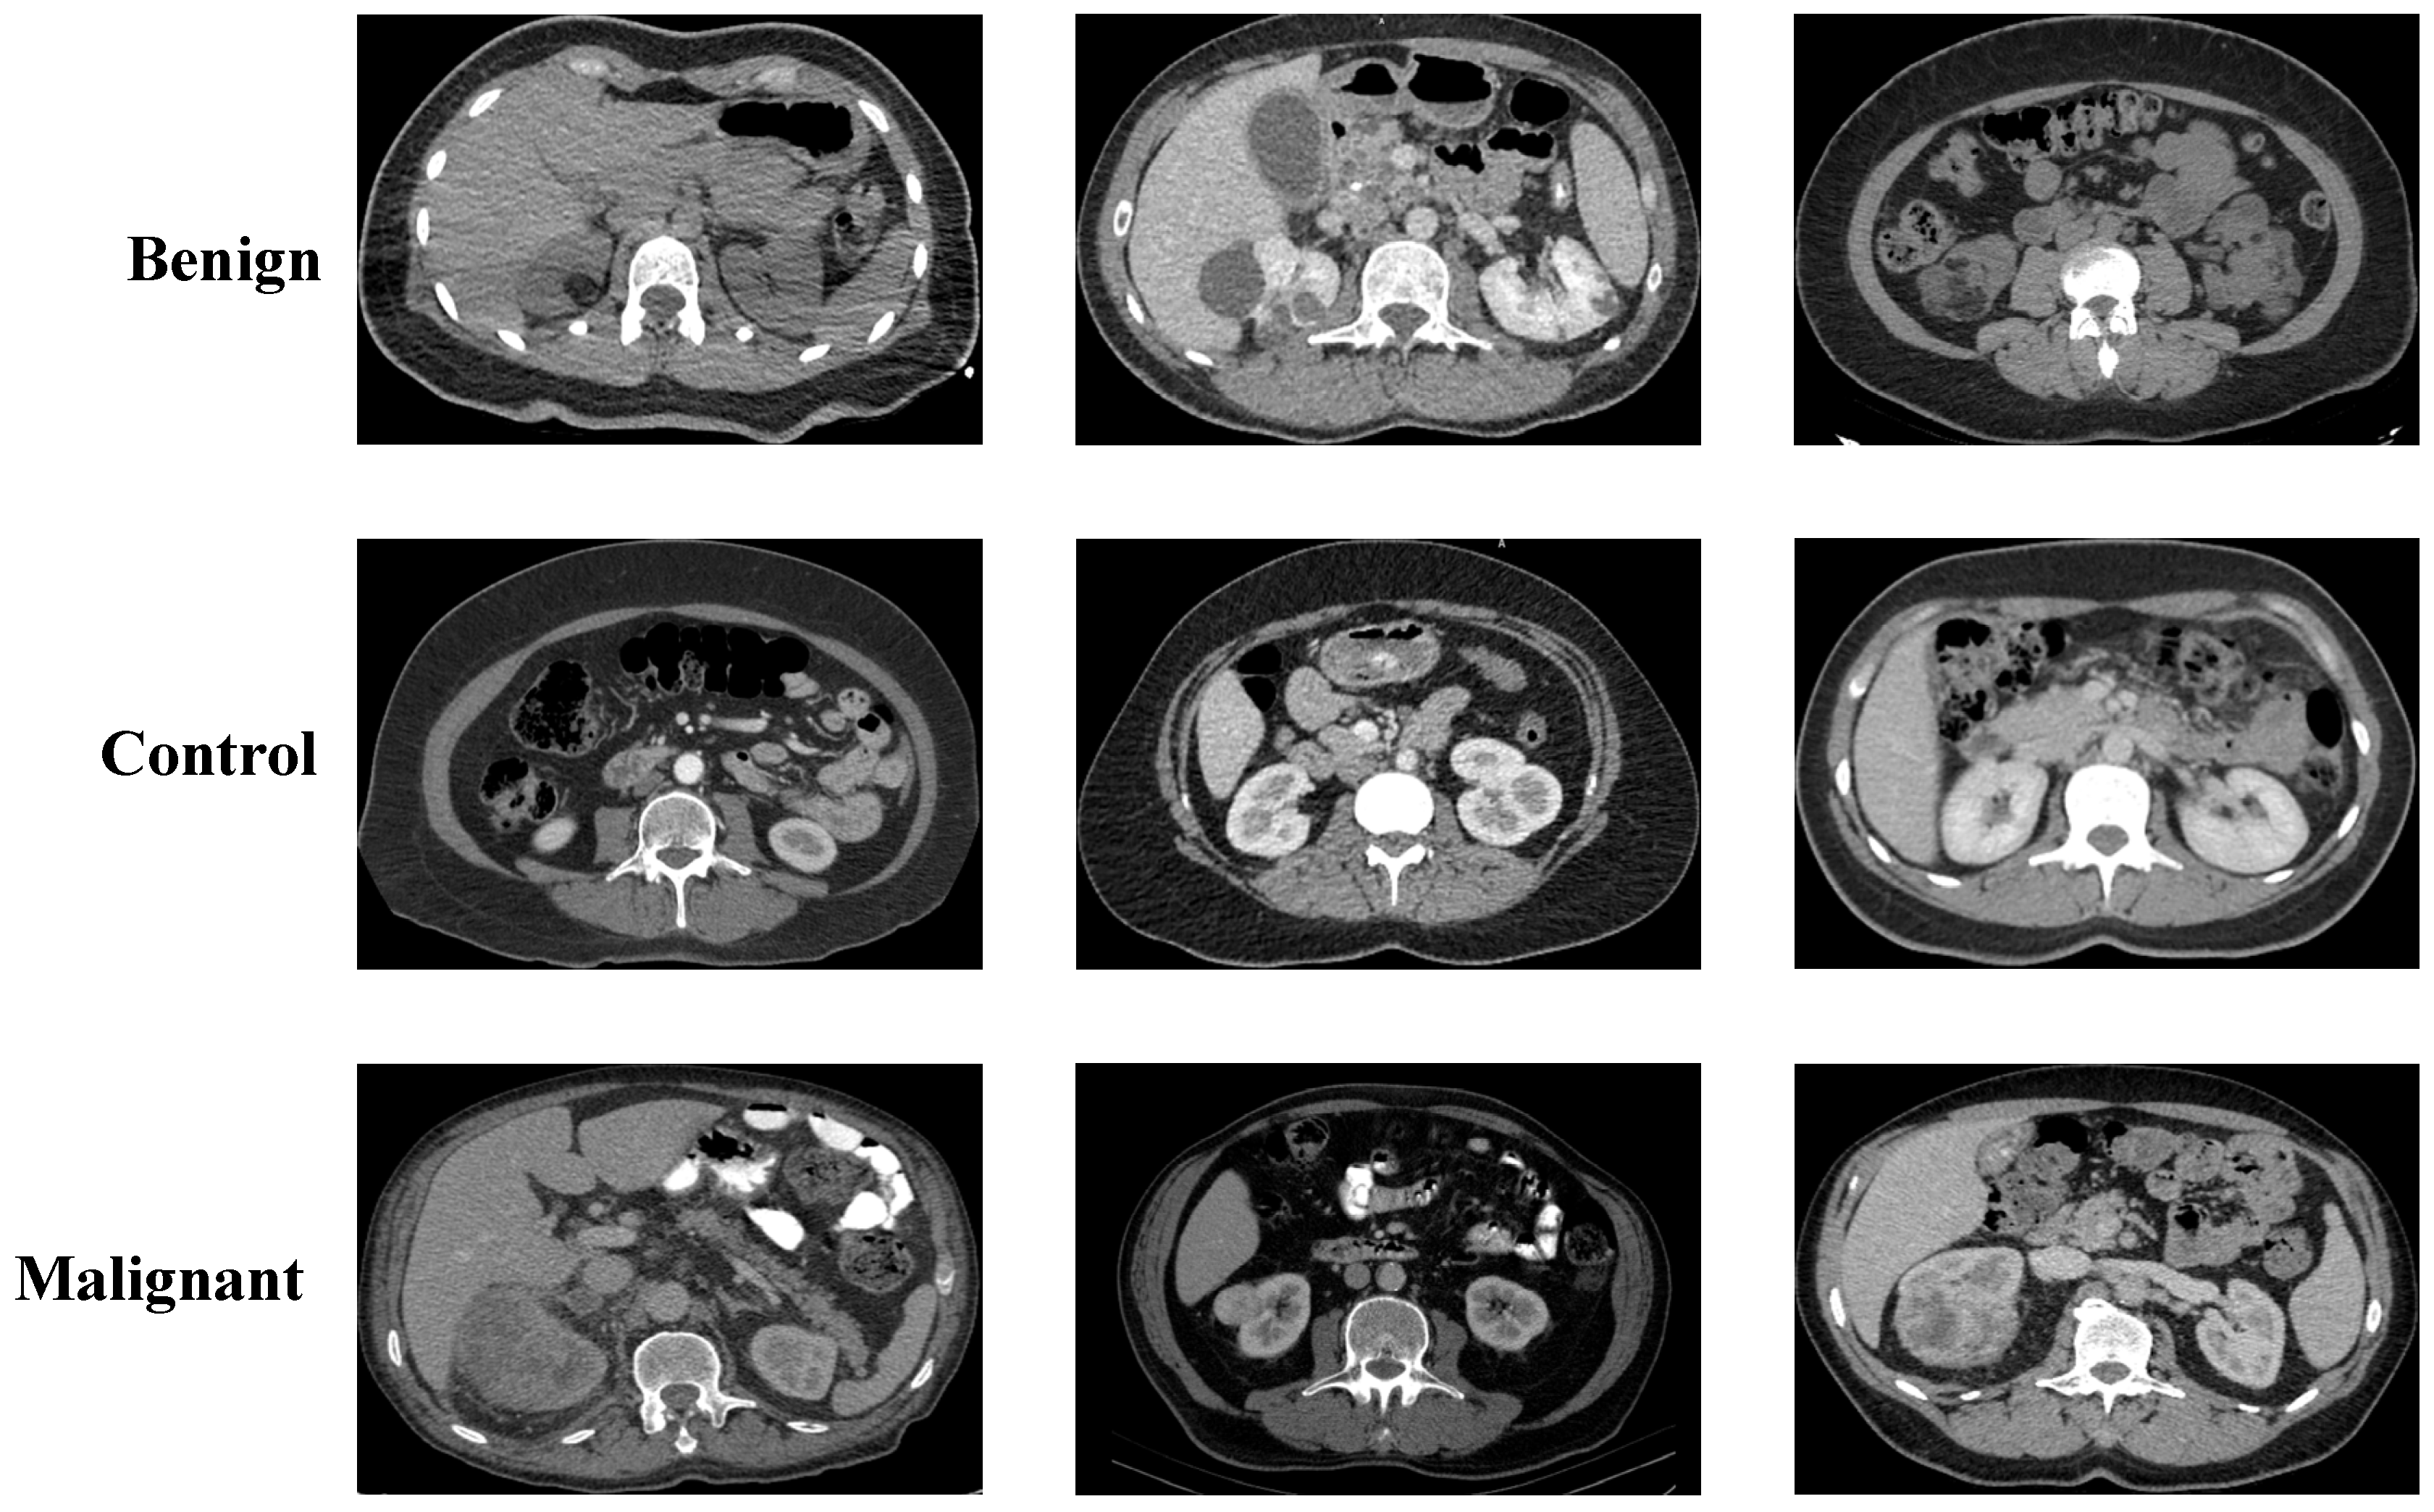

2.1. Collected Dataset

2.2. Kaggle CT KIDNEY Dataset

2.3. KAUH: Jordan Dataset